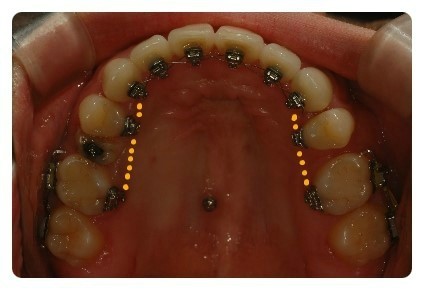

발치관계로 점선으로 표시한 부분에는 와이어를 넣지않았어요